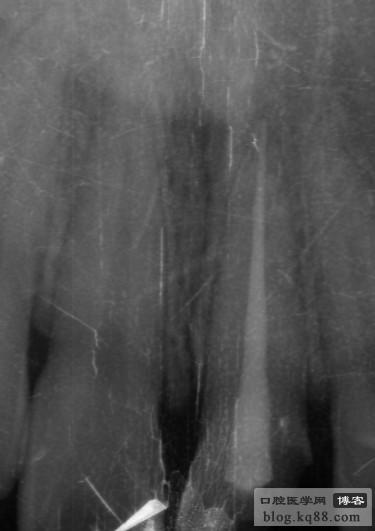

上頜是保留殘根覆蓋義齒,下頜是種植修復(fù),仔細(xì)看左上3側(cè)支根管被根充